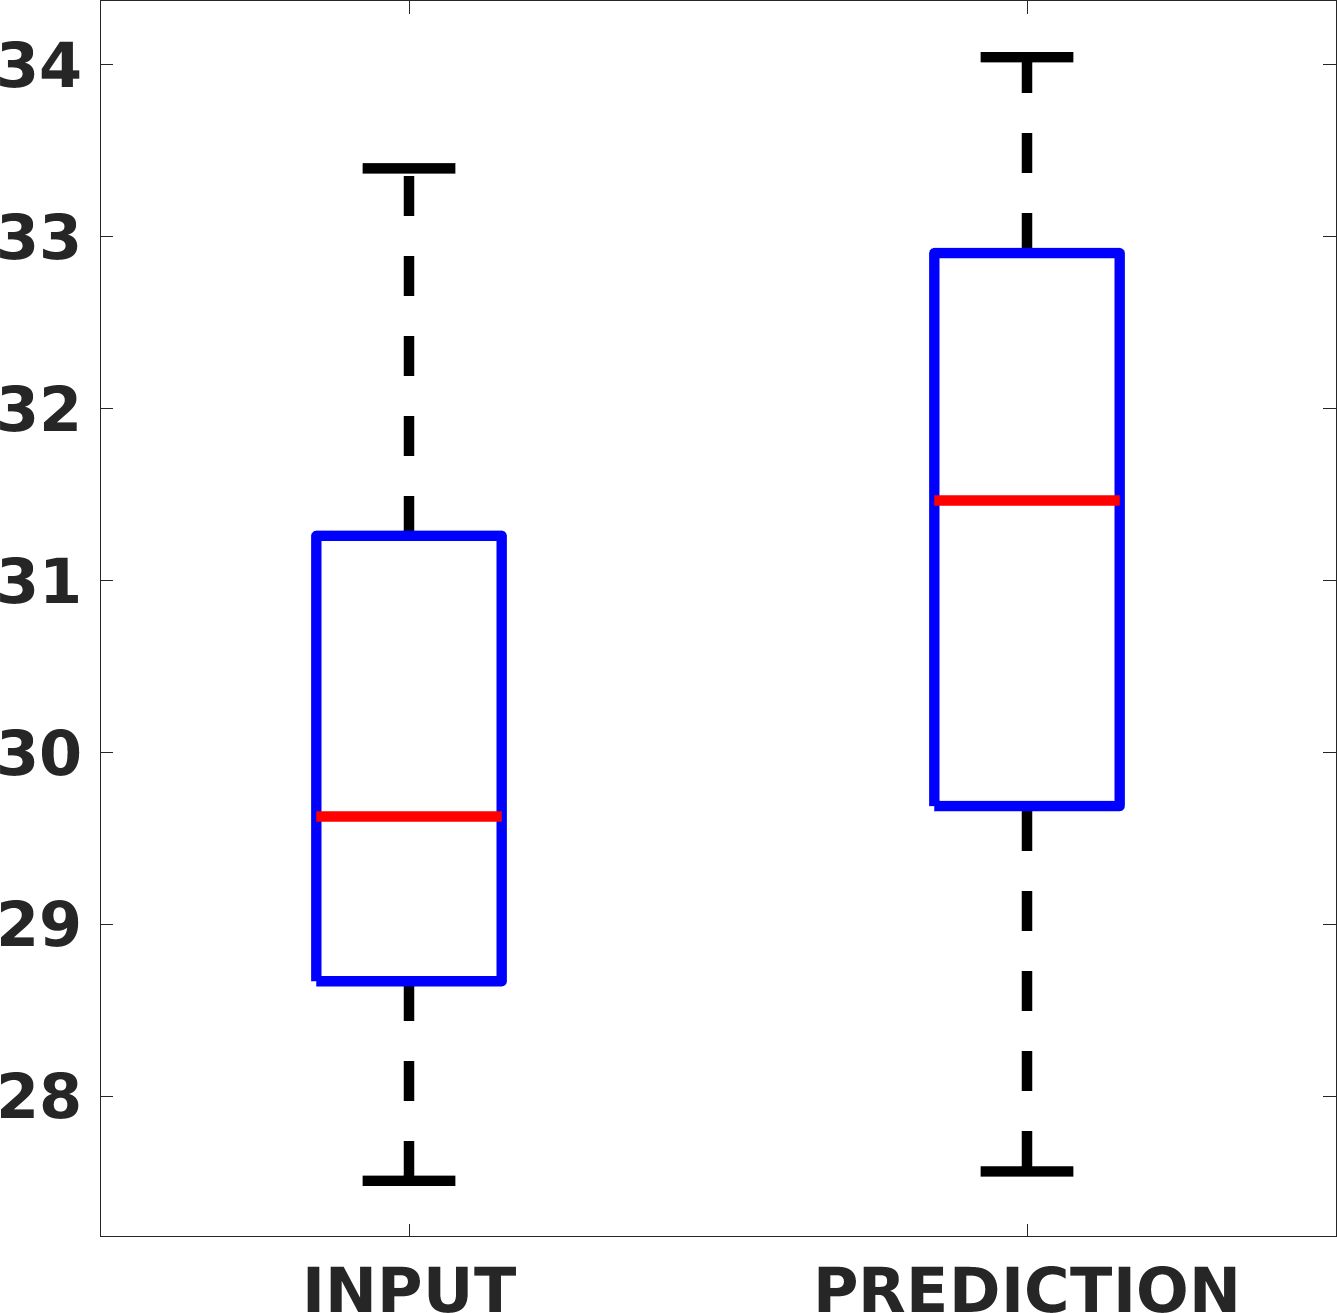

Fig. 7(a-b-c, left) shows the box plot of the statistics of the PSNR on three different anatomical districts, comparing the target images with the prediction and the cubic convolution, respectively. The metrics are computed on a data set of 200 images of the same district and with the same up-sampling factor. We report that the PSNR median value improves of on obstetric 2X raw images, on cardiac 2X raw images, and on abdominal raw 4X images.

Fig. 7(a-b-c, right) shows the histogram of the absolute value of the error with respect to the target image, of the prediction and Cubic convolution results, respectively. The histograms show the number of pixels where the prediction error is lower than 5 (i.e., the first bin of the histogram), which means very similar to the target when visually analysing the images. From the Cubic convolution to the predicted images, this value increases of on obstetric 4X raw images, on cardiac 4X raw images, and on abdominal 4X raw images.